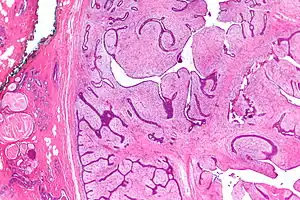

Phyllodes tumors (from Greek: phullon), are a rare type of biphasic fibroepithelial mass that form from the periductal stromal and epithelial cells of the breast.[1] They account for less than 1% of all breast neoplasms.[2] They were previously termed cystosarcoma phyllodes, coined by Johannes Muller in 1838, before being renamed to phyllodes tumor by the World Health Organization in 2003.[3] Phullon, which means "leaf" in Greek, describes the unique papillary projections characteristic of phyllodes tumors on histology.[1] Diagnosis is made via a core-needle biopsy and treatment is typically surgical resection with wide margins (>1 cm), due to their propensity to recur.[4]

| Micrograph of a phyllodes tumor (right of image) with the characteristic long clefts and myxoid cellular stroma. Normal breast and fibrocystic change are also seen (left of image). H&E stain. |